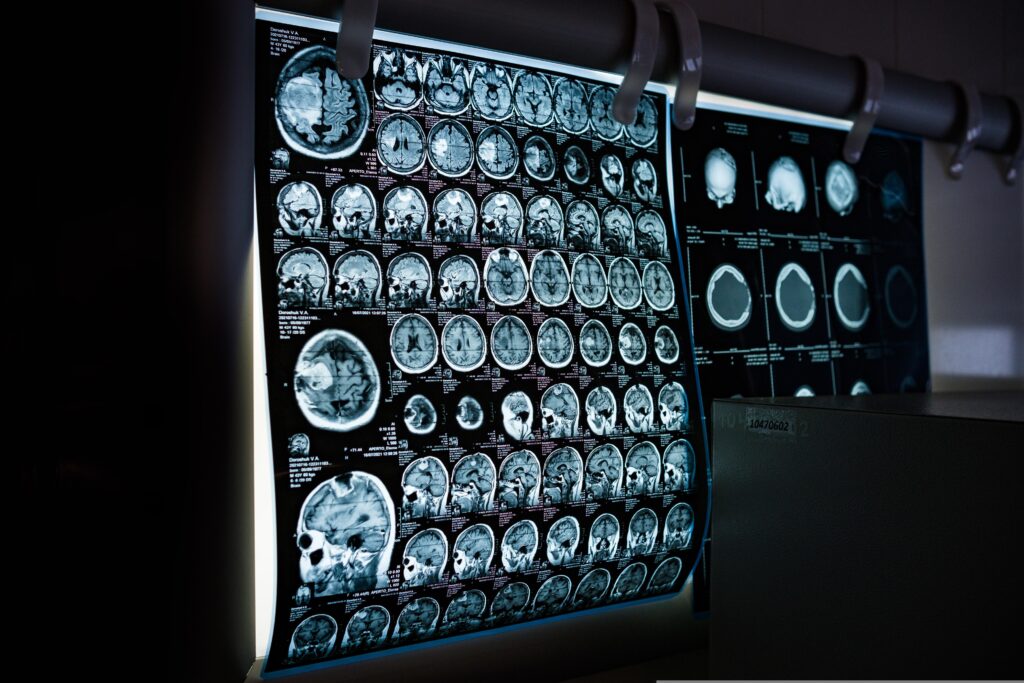

アルツハイマー病は、高齢者に最も多く見られる認知症の一種であり、記憶障害や判断力の低下を引き起こす進行性の神経変性疾患です。

この疾患の原因として長年有力視されてきたのが「アミロイド仮説」です。

これは、脳内に蓄積する「アミロイドβ」というタンパク質が神経細胞の機能を障害し、最終的に認知機能の低下を招くという考え方です。

アミロイドとは、異常に折りたたまれたタンパク質が凝集してできる物質であり、アルツハイマー病患者の脳では細胞間に「プラーク」と呼ばれる塊として蓄積することが知られています。